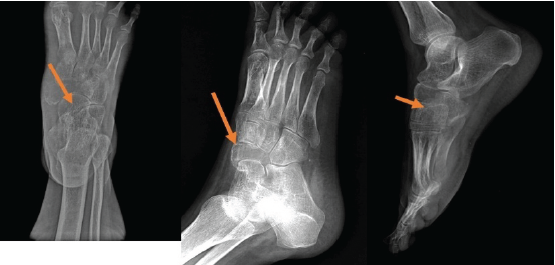

A Fig. 1 the arrow head indicating the swelling Fig. 1 the arrow head indicating the swelling 6 year old female came with complaints of pain in right foot since 1 year, swelling in the right foot since 6 months. Patient is unable to bear weight on the affected foot.

Figure 1: The arrow head indicating the swelling.

Swelling present over the dorsomedial aspect of right foot 3 × 3 × 1 cm in size, hard in consistency, skin over the swelling is free.

Tenderness present over swelling, inversion, and eversion of the foot painful.

Routine radiological investigations revealed a large globular lesion in the navicular bone (Fig. 2). Computed tomography scan (Fig. 3, 4) and magnetic resonance imaging (Fig. 5) modalities revealed an expansile lesion in the navicular bone lobulated extension of lesion on the plantar aspect and adjacent tarsal bones (cuneiform, cuboid) and intertarsal joints. We thus had a suspicion of a malignant lesion? Round cell tumour? Ewing’s sarcoma. On following up with histopathology, the histopathological report of lesion determined giant cell tumor (GCT).

Figure 2: Routine X-rays.